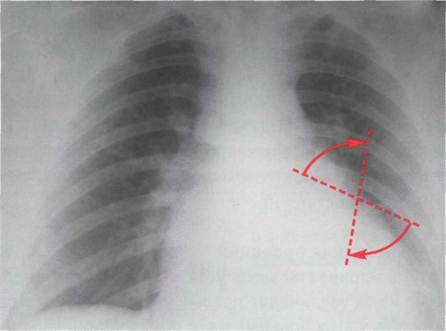

Изменения рентгенографической конфигурации сердца в переднезадней проекции обусловлены, прежде всего, сглаживанием талии из-за увеличения полости левого предсердия и его ушка с расширением третьей дуги по левому контуру сердечной тени

Рентгенограмма сердца в переднезадней проекции больного с митральным стенозом. Митральная конфигурация сердца

Увеличение размеров сердечной тени при митральном стенозе не столь велико, как при митральной недостаточности. В большинстве случаев поперечник сердца увеличивается равномерно в обе стороны. Степень выбухания и протяженность третьей дуги соответствуют размерам ушка левого предсердия. За - падение третьей дуги отмечается у больных, перенесших закрытую митральную комиссуротомию, что соответствует маленькому, сморщенному или перевязанному, а иногда ротированному кзади ушку левого предсердия. При западении третьей дуги можно

Предполагать тромбоз ушка левого предсердия, которое обычно сморщивается. Часто при увеличении левого предсердия выявляется добавочная дуга на фоне верхней половины сердечной тени близ правого контура или она непосредственно участвует в образовании правого контура. Добавочная дуга обрисовывает нижний правый контур левого предсердия, что на фоне тени сердца выглядит как тень двойной интенсивности из-за значительного увеличения переднезаднего размера левого предсердия. Особенностью сердечной тени у больных митральным стенозом в переднезадней проекции является хорошая дифференциация дуг левого контура из-за подчеркнутой выпуклости ушка левого предсердия и легочной артерии.

Вследствие увеличения третьей дуги размеры дуги левого желудочка могут быть относительно уменьшены. Иногда верхушка сердца слегка приподнимается над диафрагмой из-за оттеснения ее влево и вверх правым желудочком, размеры которого при высокой степени легочной гипертензии преобладают над размерами левого желудочка .